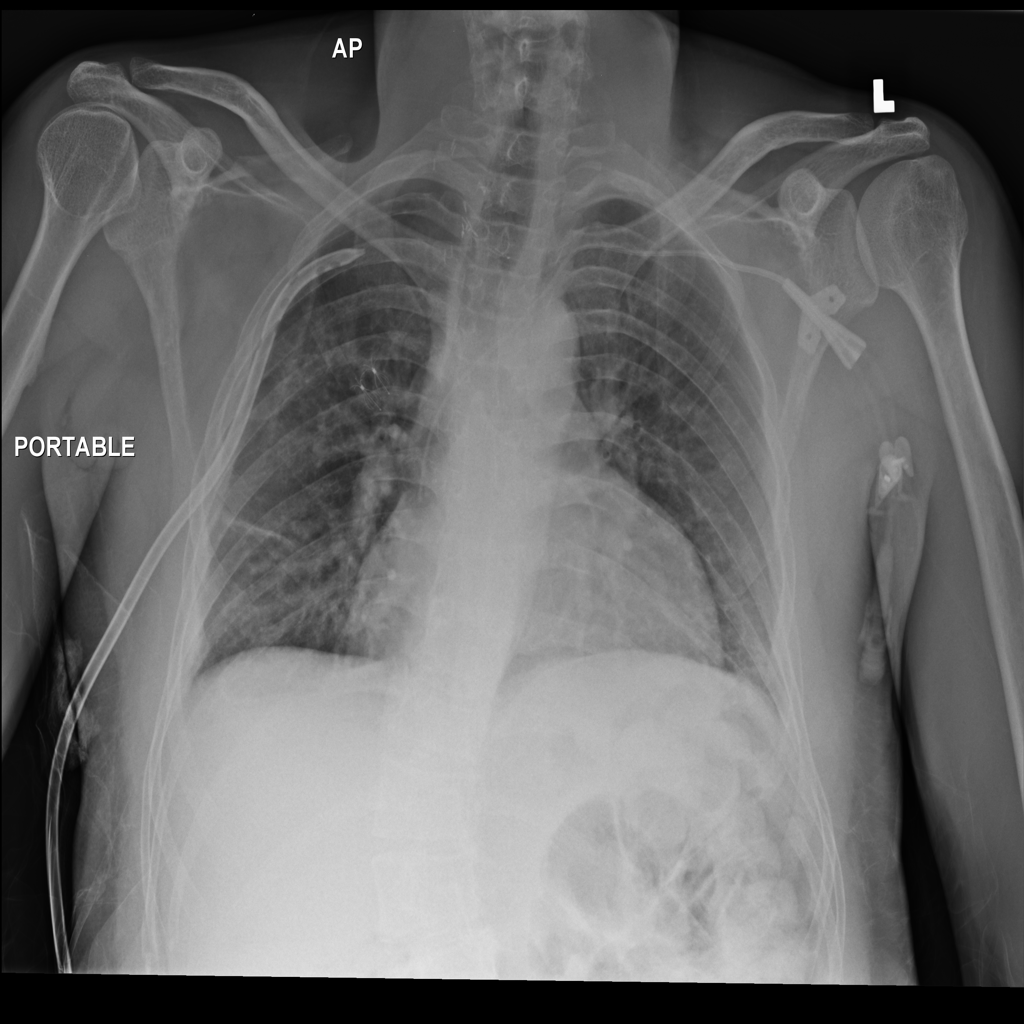

PAT-DB80 · IMG-001Atelectasis

PAT-DB80 · IMG-001

PA